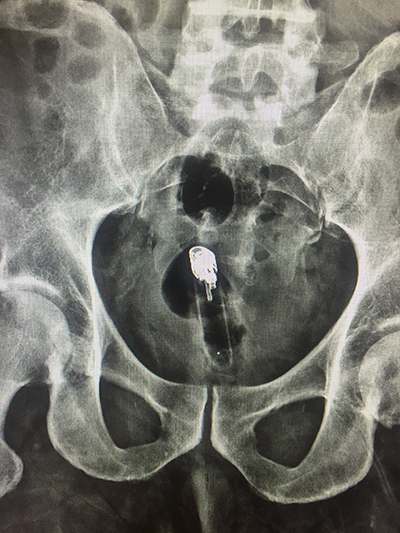

Adult male currently incarcerated, referred to the Emergency Department for lower back pain with risk factor of IV drug abuse. Patient was sent for MRI when we received a call from the radiology technician that 'something doesn't look right' on the scout film.